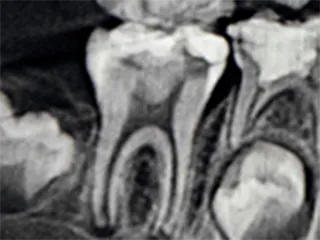

根管は一人ひとり形が違い、弯曲や側枝と呼ばれる入り組んだ構造も含まれており、どのような構造になっているかを正確に把握した上で、神経を精緻に処理をすることが重要です。

歯科用コーンビームCTを使用し、根管の内部を3次元的に解剖したように隅々まで構造を把握することで、歯髄を取る必要な部分がはっきり分かり、勘や経験に頼らず、的確に処置を進められます。